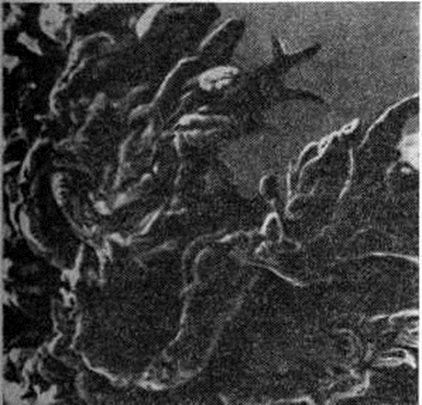

В суставах при развёрнутой клинические, картине заболевания обнаруживается ворсинчатое разрастание синовиальной оболочки (рисунок 1), в части случаев наползающей в виде паннуса на поверхность суставного хряща. При этом в суставном хряще определяются эрозии, трещины, щели; его остатки сухие и зернистые на вид. В суставных полостях обнаруживается увеличенное количество вязкой мутной синовиальной жидкости, постоянно отмечается утолщение и склероз суставной капсулы, имеются фиброзные спайки. Полная облитерация суставной полости спайками ведёт к развитию фиброзного анкилоза (смотри полный свод знаний). Пролиферация остеоидной ткани сопровождается развитием остеофитов (смотри полный свод знаний) и костных анкилозов.

В гистологический картине синовита выделяют следующие изменения: 1) поражение сосудов микроциркуляторного русла; 2) гиперплазию и гипертрофию синовиальных клеток; 3) воспалительную клеточную инфильтрацию; 4) разрастание грануляционной ткани, склероз, липоматоз синовиальной собственной пластинки. Повышается проницаемость стенок сосудов микроциркуляторного русла, сопровождающаяся выходом фибринозного экссудата и образованием очагов фибриноида в синовиальной собственной пластинке и фибриноподобных наложений на поверхности синовиальной оболочки. Иммуноморфологически в очагах фибриноида и в фибриноподобных наложениях выявляются фибрин, иммуноглобулины (G, А, М) и С3-фракция комплемента. При обострении воспаления постоянно отмечается продуктивный или продуктивно-деструктивный васкулит с фиксацией в сосудистой стенке иммуноглобулинов и комплемента. В глубоких слоях синовиальной оболочки (смотри полный свод знаний) изредка определяются ревматоидные узелки — небольшие участки фибриноидного некроза, окружённые макрофагами и лимфоцитами. В 80% случаев встречается гиперплазия и гипертрофия синовиоцитов с характерным палисадообразным их расположением (рисунок 2). С помощью электронно-микроскопического исследования обнаружено, что гипертрофия синовиоцитов происходит за счёт гиперплазии их органелл, особенно зернистой эндоплазматической сети, полисом, аппарата Гольджи и лизосом (рисунок 3). В гиперплазии ворсинчатого слоя синовиальной оболочки участвуют синовиоциты всех трёх типов (А, В и С). На ранних стадиях обострения воспаления клеточная инфильтрация в синовиальной оболочке скудная, представлена лимфоцитами, макрофагами и полиморфно-ядерными лейкоцитами. В дальнейшем отмечается лимфоидно-плазмоцитарная инфильтрация (рисунок 4), иногда с формированием лимфоидных фолликулов. Параллельно при иммунофлюоресцентном изучении Т и В-лимфоцитов синовиальной оболочки при Ревматоидный артрит Банкхерст (A. D. Bankhurst) с соавторами (1976) выявил преобладание Т-лимфоцитов. В синовиальной оболочке отмечается значительная пролиферация фибробластов. В синовиальной собственной пластинке и фиброзном слое наблюдается разрастание грануляционной ткани с исходом в склероз (смотри полный свод знаний) и липоматоз (смотри полный свод знаний).